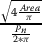

In this section, we examine fuzzy and non-fuzzy clustering algorithms and compare them with respect to their discrimination of overlapped nuclei. We use the k-means technique for the non-fuzzy approach, which was first introduced by McQueen [14]. The goal of this approach is to partition n-numbered observations into k sets. Since this method is non fuzzy, each of the pattern clusters have one center at any given time. This algorithm updates the centroids with each iteration to minimize the within-cluster sum of the squares, which is defined as

![]() |

1 |

where the

term indicates the distance between an observation and the

cluster’s centroid. With this approach, the algorithm assigns observations to

clusters according to their distance from cluster centers, and updates the

centroids of new members. A block diagram of this process is shown in

Figure 6a.